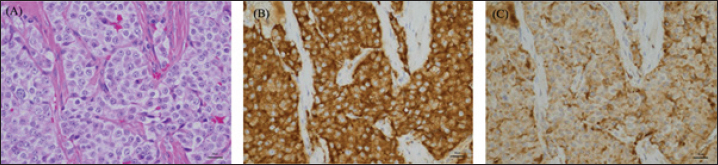

There was no obvious bleeding or air leakage at the resection surface. The chest was closed, and the surgery was terminated. The dog was in good postoperative condition and was discharged in the post-operative 3 day. Histopathological examination revealed cuboidal to polygonal cells densely arranged in a cord-like or band-like pattern. Proliferating cells had round-to-oval nuclei and moderate cytoplasmic, acidophilic, and basophilic granularity. Tumor cell infiltration was observed in the blood vessels. Immunohistochemical staining showed that the mass was strongly positive for the neuroendocrine markers Synaptophysin and Chromogranin A, diagnosed as a neuroendocrine carcinoma (Fig. 4).

Fig. 4. High-power microscopic images of the pulmonary mass. (A) On H&E, the mass is composed of densely packed polyhedral cells compartmentalized by a fibrovascular stroma. The neoplastic cells have round nuclei and moderately abundant, eosinophilic granular cytoplasm. There is moderate anisokaryosis, and nuclear chromatin is coarsely granular with 1-2 small nucleoli. The neoplastic cells are diffusely positive for Synaptophysin (B) and Chromogranin A (C).